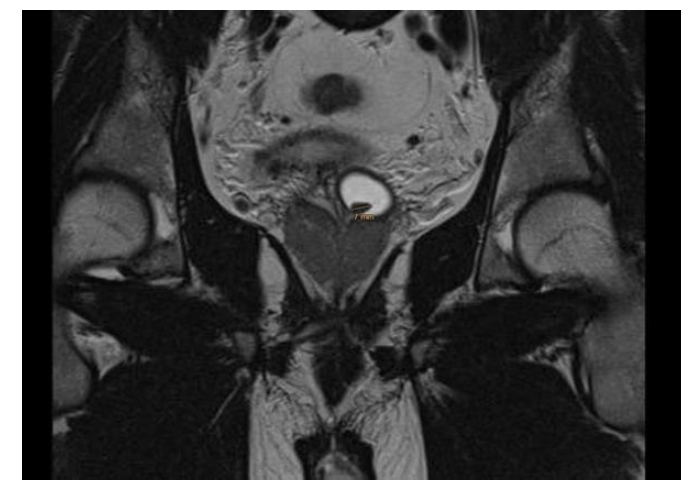

Next, we checked things out further with a pelvic MRI that confirmed a roughly 1.5 cm calculus lodged in the enlarged vesicle (Figure 2).

Figure 2: In the T2 sequences of MR imaging, it was found that a stone ca 7 mm.